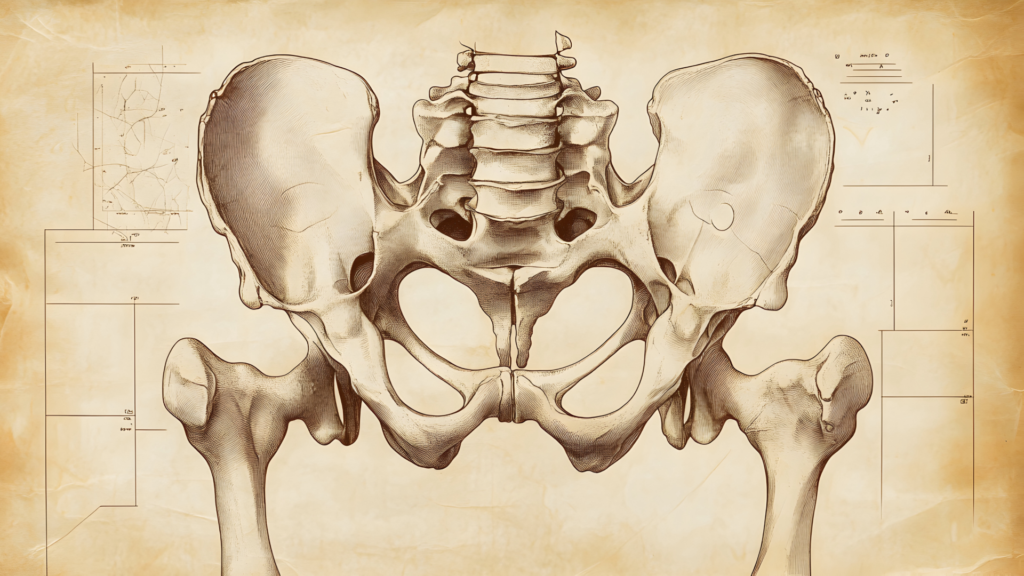

Прежде чем погрузиться в методы диагностики, важно иметь базовое представление о структуре позвоночника. Поясничный отдел состоит из пяти позвонков, между которыми расположены межпозвоночные диски, выполняющие роль амортизаторов. Вокруг позвонков расположены связки и мышцы, обеспечивающие поддержку и движение. Знание этой структуры помогает понять, где именно может возникать проблема, вызывающая хруст.